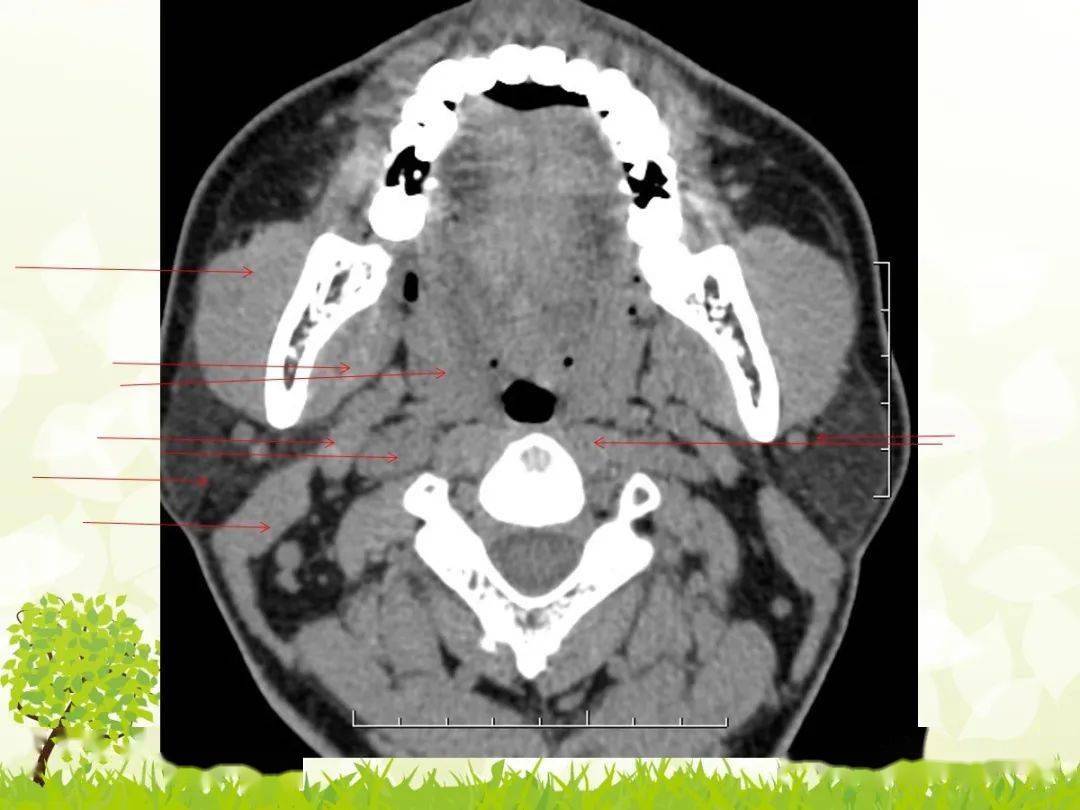

图解颈部ct影像阅片及诊断报告要点

影像医学和核医学讨论版 面颈 声门上型喉癌: 部位:声带以上会厌,杓会

(2)声门上区:声带上缘以上的喉腔,包括会厌,杓会厌皱襞,杓状软骨,室带

右侧室带,杓会厌皱襞和梨状窝受侵图3-5-15 声门下区癌ct平扫通过环状

影像解剖喉部ct解剖简单